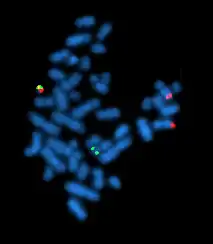

A metaphase cell positive for the BCR/ABL rearrangement using FISH

Philadelphia translocation t(9;22)(q34;q11.2) seen in chronic myelogenous leukemia.

Acquired cytogenetics: In 1960, Peter Nowell and David Hungerford[21] discovered a small chromosome in the white blood cells of patients with Chronic myelogenous leukemia (CML). This abnormal chromosome was dubbed the Philadelphia chromosome - as both scientists were doing their research in Philadelphia, Pennsylvania. Thirteen years later, with the development of more advanced techniques, the abnormal chromosome was shown by Janet Rowley to be the result of a translocation of chromosomes 9 and 22. Identification of the Philadelphia chromosome by cytogenetics is diagnostic for CML. More than 780 leukemias and hundreds of solid tumors (lung, prostate, kidney, etc.) are now characterized by an acquired chromosomal abnormality, whose prognostic value is crucial. The identification of these chromosomal abnormalities has led to the discovery of a very large number of "cancer genes" (or oncogenes). The increasing knowledge of these cancer genes now allows the development of targeted therapies, which transforms the prospects of patient survival. Thus, cytogenetics has had and continues to have an essential role in the progress of cancer understanding. Large databases (Atlas of Genetics and Cytogenetics in Oncology and Haematology, COSMIC cancer database, Mitelman Database of Chromosome Aberrations and Gene Fusions in Cancer) allow researchers and clinicians to have the necessary corpus for their work in this field.